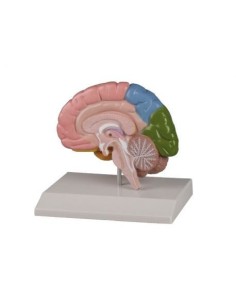

Découvrez le monde de l'anatomie avec des modèles anatomiques de précision

Bienvenue sur Tuttoanatomia.it, le portail de référence en Italie pour l'achat de modèles anatomiques, de posters, de lits portables, de simulateurs médicaux et de littérature spécialisée. Grâce à nos modèles anatomiques de pointe de 3B Scientific et Erler Zimmer, nous offrons une expérience d'apprentissage inégalée.

Des modèles anatomiques détaillés pour tous les besoins

Du crâne en 22 parties à verrouillage magnétique aux modèles de colonne vertébrale, des modèles d'articulation aux modèles de cœur, chaque pièce de notre collection est conçue pour une immersion totale dans l'étude de l'anatomie humaine. Nos modèles, réalisés à partir de scans d'os réels, garantissent une expérience tactile authentique et une fidélité de poids presque identique aux originaux.

Indispensables aux étudiants comme aux professionnels, nos modèles anatomiques sont des outils pédagogiques qui permettent d'observer les structures anatomiques avec précision, en évitant les dissections ou les études invasives. Ils sont également utiles pour expliquer les pathologies aux patients, ce qui rend la communication plus efficace et permet de gagner un temps précieux.